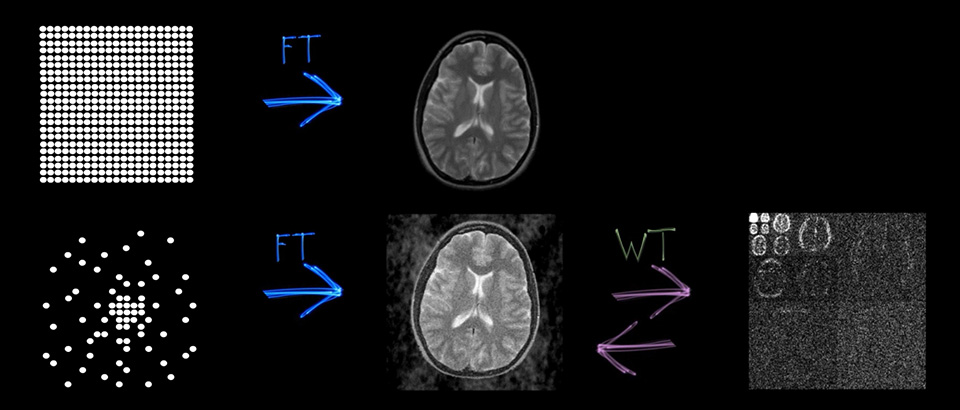

画質は同等のまま高速化が可能1

2Dおよび3Dのあらゆる撮像画像に適用可能

空間分解能が最大64%向上1